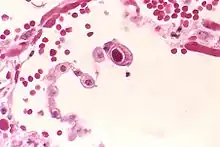

| Typical "owl eye" intranuclear inclusion indicating CMV infection of a lung pneumocyte[1] | |

- ↑ Mattes FM, McLaughlin JE, Emery VC, Clark DA, Griffiths PD (August 2000). "Histopathological detection of owl's eye inclusions is still specific for cytomegalovirus in the era of human herpesviruses 6 and 7". Journal of Clinical Pathology. 53 (8): 612–4. doi:10.1136/jcp.53.8.612. PMC 1762915. PMID 11002765.